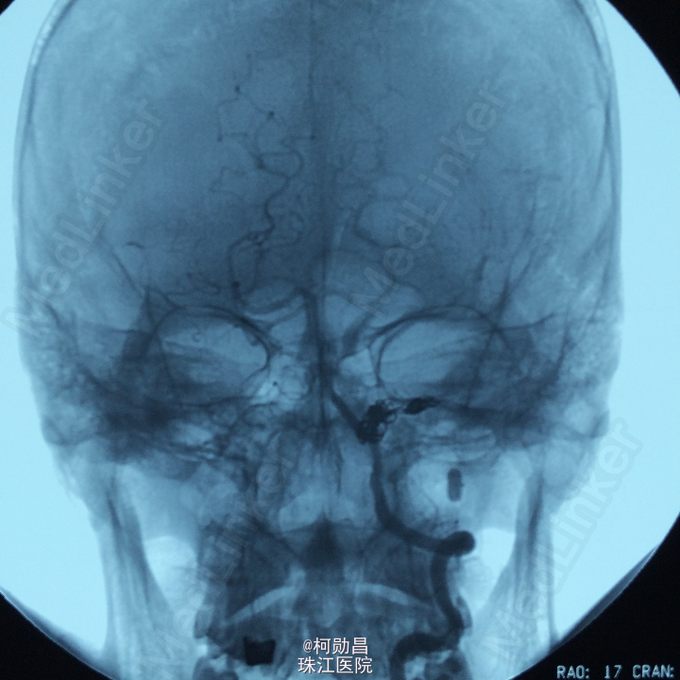

诊断:颈内动脉假性动脉瘤破裂 处理:急诊行DSA检查,提示颈内动脉海绵窦段动脉瘤形成并破裂向鼻腔引流,予血管内栓塞治疗,将动脉瘤腔堵塞,患者出血停止。